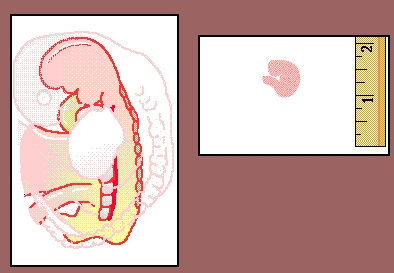

贊達尼長老說:"我們現在看到的這個像被咬過一口的胚胎,長度只有一釐米,其中有許多是前面提及或已證明了的東西。我們所看到 胚胎外型像一張弓,在這張弓的尾部有一個痕跡,仿佛人被鑄成像被咬過一口的東西,同時可以看到一些鼓起的或是有溝漕的表皮,它們平滑而寬闊,這就像被咬過一口的形狀。" 然後長老又說:"如果我們將胚胎的切面拿來解釋其內部構造,就會看到一個較大的股體已被孕育成,如右圖所示,其中部分肌體已完成,但有一部分在孕育之中,如果我們想敘述這個像被咬過一口的胚胎,還是聽聽瑪爾夏路博士的話吧!" |

"我們說什麼呢?我們說它已被造化好了?這是根據已孕育生成的部分肌體而言;我們說它還未被造化好?事實上它的部分肌體還沒完全生成。"博士接著說:"但我們必須對這個像被咬過一口的胚胎的內部肌體進行描述。這一描述就是《古蘭經》中早已指明的:然後就是已被造化和未被造化好的像被咬過一口的肉團。"他又就他的研究作了簡要的陳述:"我是一個學者,熟悉胚胎學和生物學,也能理解有關《古蘭經》中翻譯過來這兩方面的請况。就像我以前給你們所舉的例子一樣,我們可以假設:如果我是穆罕默德同時代的人,以我的學識去開展這方面的工作,只有在今天我才能描繪這些。我找不到任何證据反駁穆罕默德(求主賜福他)關於這些問題的見解,他究竟從哪裏得到這些知識的?那是全面充分的知識,也是能夠降示於穆罕默德(求主賜福他)並傳達它的。"3 "每一種預告都有他實現的時間。你們不久會知道的。" (6:67)